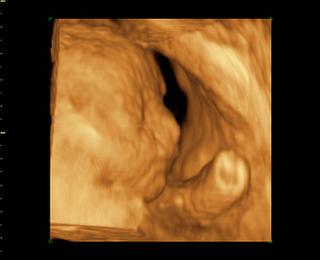

@bv_alexandra 3Dčko je skôr pre potešenie, morfologický UV je na diagnostiku, vidno na ňom orgány a kosti bábätka, vidno chlopne srdiečka, je možné zmerať dĺžku kostí a tak podobne, len pre porovnanie, už som to sem dávala aj predtým a písala som o tom, pridávam ti fotky z môjho prvého tehu, tie "farebné" sú z 3Dčka tam je krásne vidieť bábätko, tváričku, črty tváre, je vidieť na koho sa podobá, ako vyzerá, na morfologickom, to je ten čiernobiely vidieť bábo "zvnútra" aby sa potvrdilo že je úplne zdravé a nemá žiadne vývojové vady, podľa dĺžky kostí ti tam aj spresnia termín pôrodu.